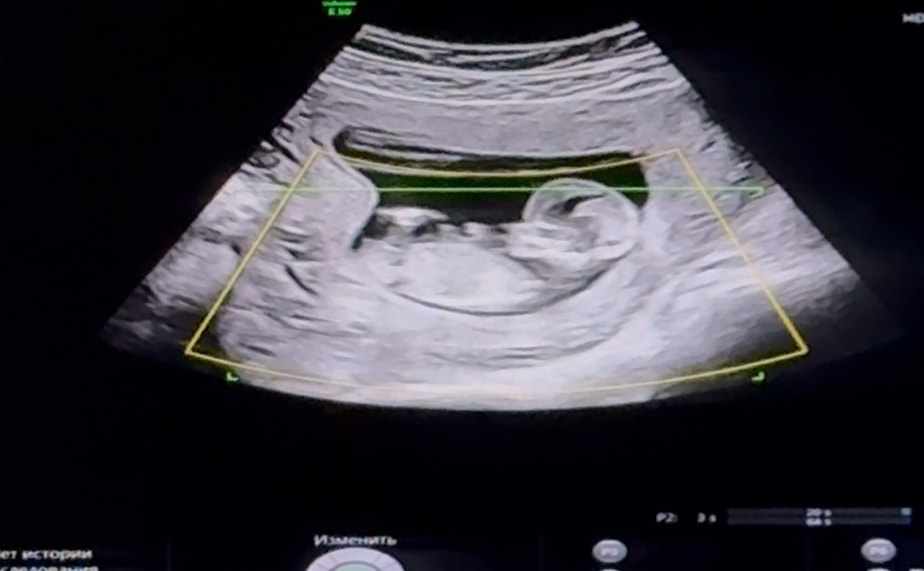

Определение пола по половому бугорку.

Нужен совет (вне обсуждений основной темы сообщества, но в рамках разумного)Всем привет! На первом скрининге сказали 95% девочка, а сегодня была на УЗИ перед отпуском, сказали, что больше похоже на мальчика 😆 Кто умеет определять по половому бугорку?